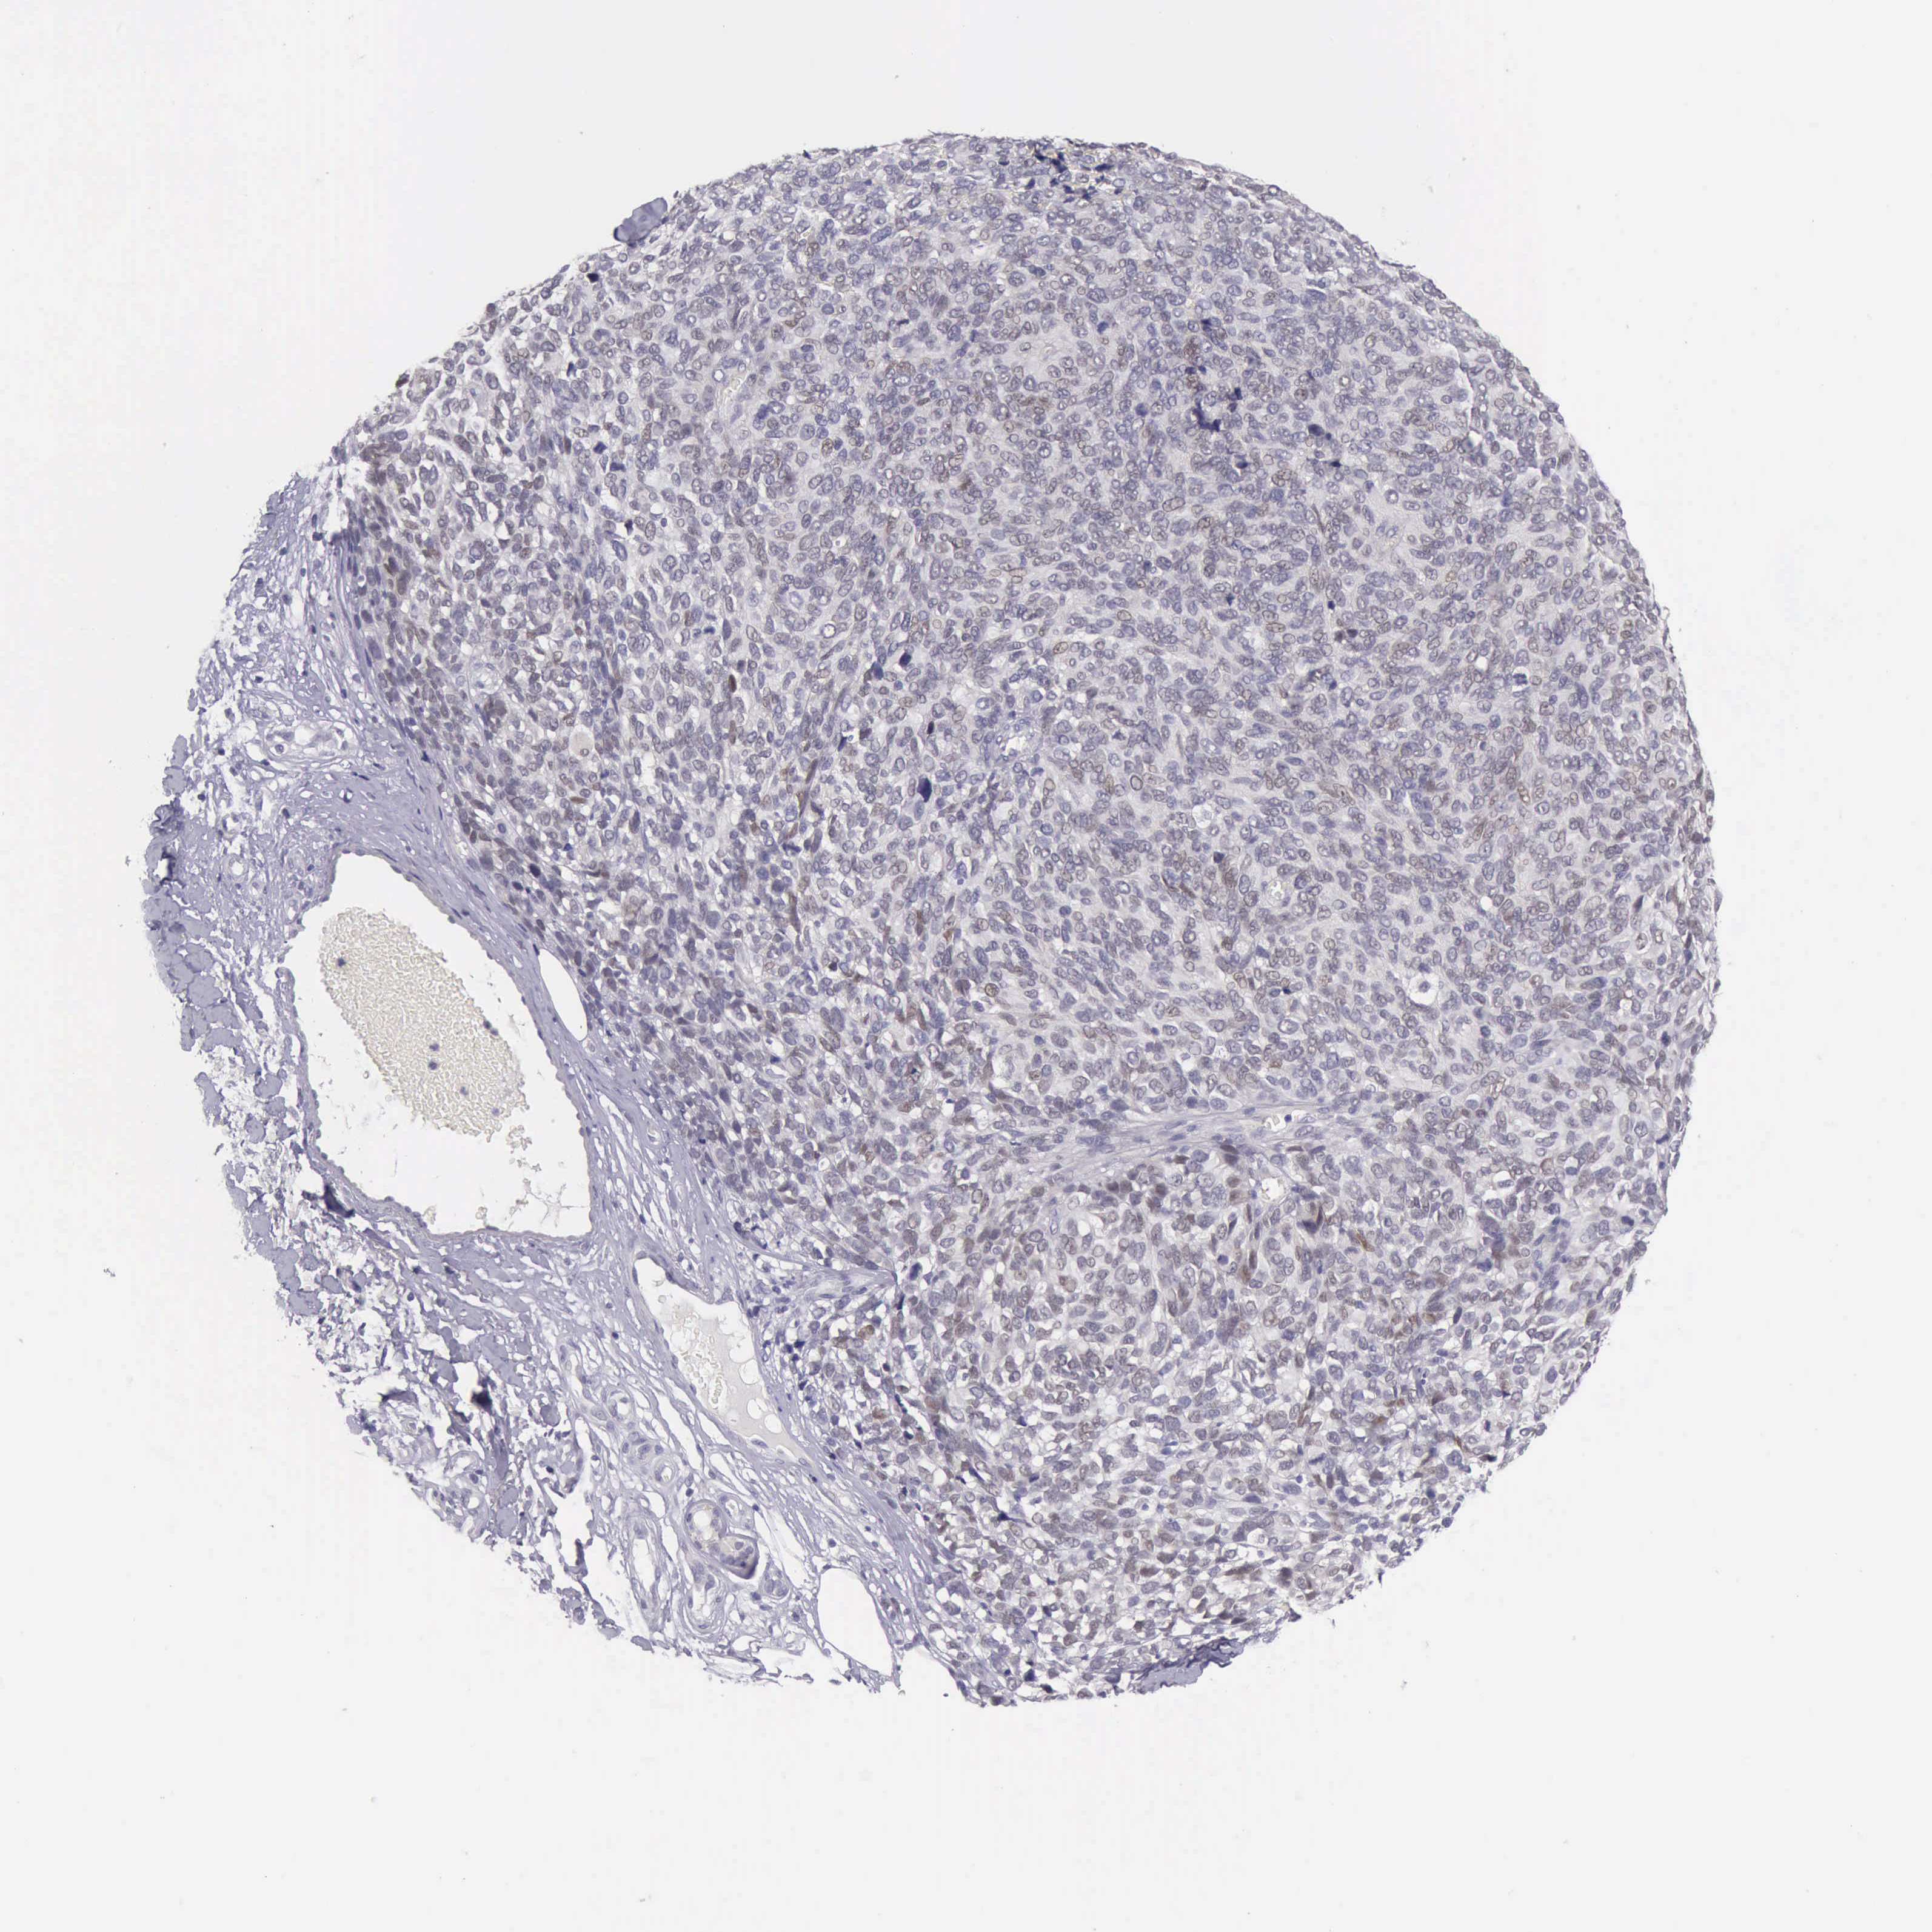

MELANOMA - Protein expressioni

A mouse-over function shows sample information and annotation data. Click on an image to view it in a full screen mode. Samples can be filtered based on level of antibody staining by selecting one or several of the following categories: high, medium, low and not detected. The assay and annotation is described here.

Note that samples used for immunohistochemistry by the Human Protein Atlas do not correspond to samples in the TCGA dataset.

Antibody stainingi

Antibody staining in the annotated cell types in the current human tissue is reported as not detected, low, medium, or high, based on conventional immunohistochemistry profiling in selected tissues. This score is based on the combination of the staining intensity and fraction of stained cells.

Each image is clickable and will lead to virtual microscopy that enables deeper exploration of all samples and also displays staining intensity scores, fraction scores and subcellular localization as well as patient and tissue information for each sample.

Antibody HPA001056

Antibody CAB005081

Staining

High

Medium

Low

Not detected

Intensity

Strong

Moderate

Weak

Negative

Quantity

>75%

75%-25%

<25%

None

Location

Nuclear

Cytoplasmic/membranous

Cytoplasmic/membranous,nuclear

Malignant melanoma, NOS

Malignant melanoma, Metastatic site